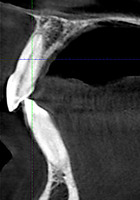

Через 12 месяцев (рис. 7а-г) на срезах компьютерной томограммы 11-ый и 13-ый зубы находятся в костной ткани, при этом костные пики и перегородки укрепились, объем их увеличился; вестибулярно заметен объем костной массы, предположительно компактной формации, исходя из электронной плотности участка. Этим объясняется отсутствие рецидива при лечении рецессии десны как в случае применения аутотрансплантата, также и ТМО (dura mater).